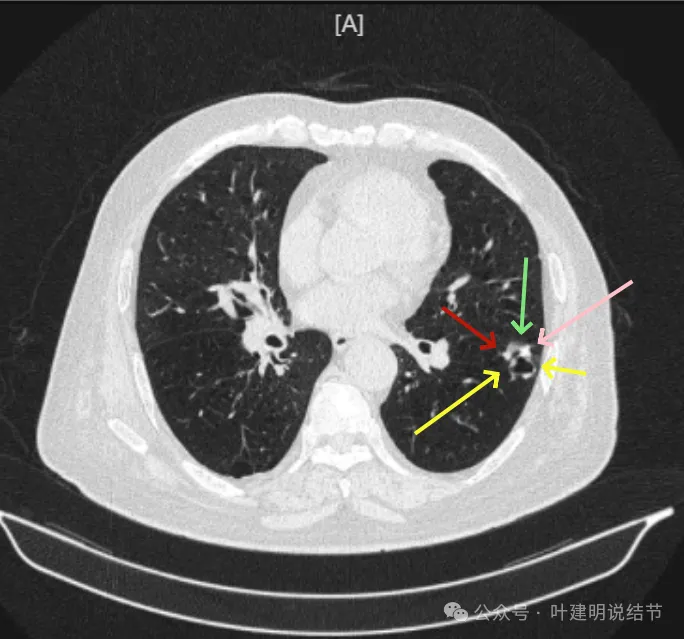

冠状位见病灶基本实性,小血管进入明显,囊壁厚薄不均,囊腔内壁不光滑,表面浅分叶。

矢状位显示较强的收缩力的样子,表面明显棘突的样子,而且囊壁密度杂乱,伴浅分叶征以及胸膜牵拉征。

前后最明显层面对比:

间隔才三个月,明显感觉更不舒服,更像恶性了些。